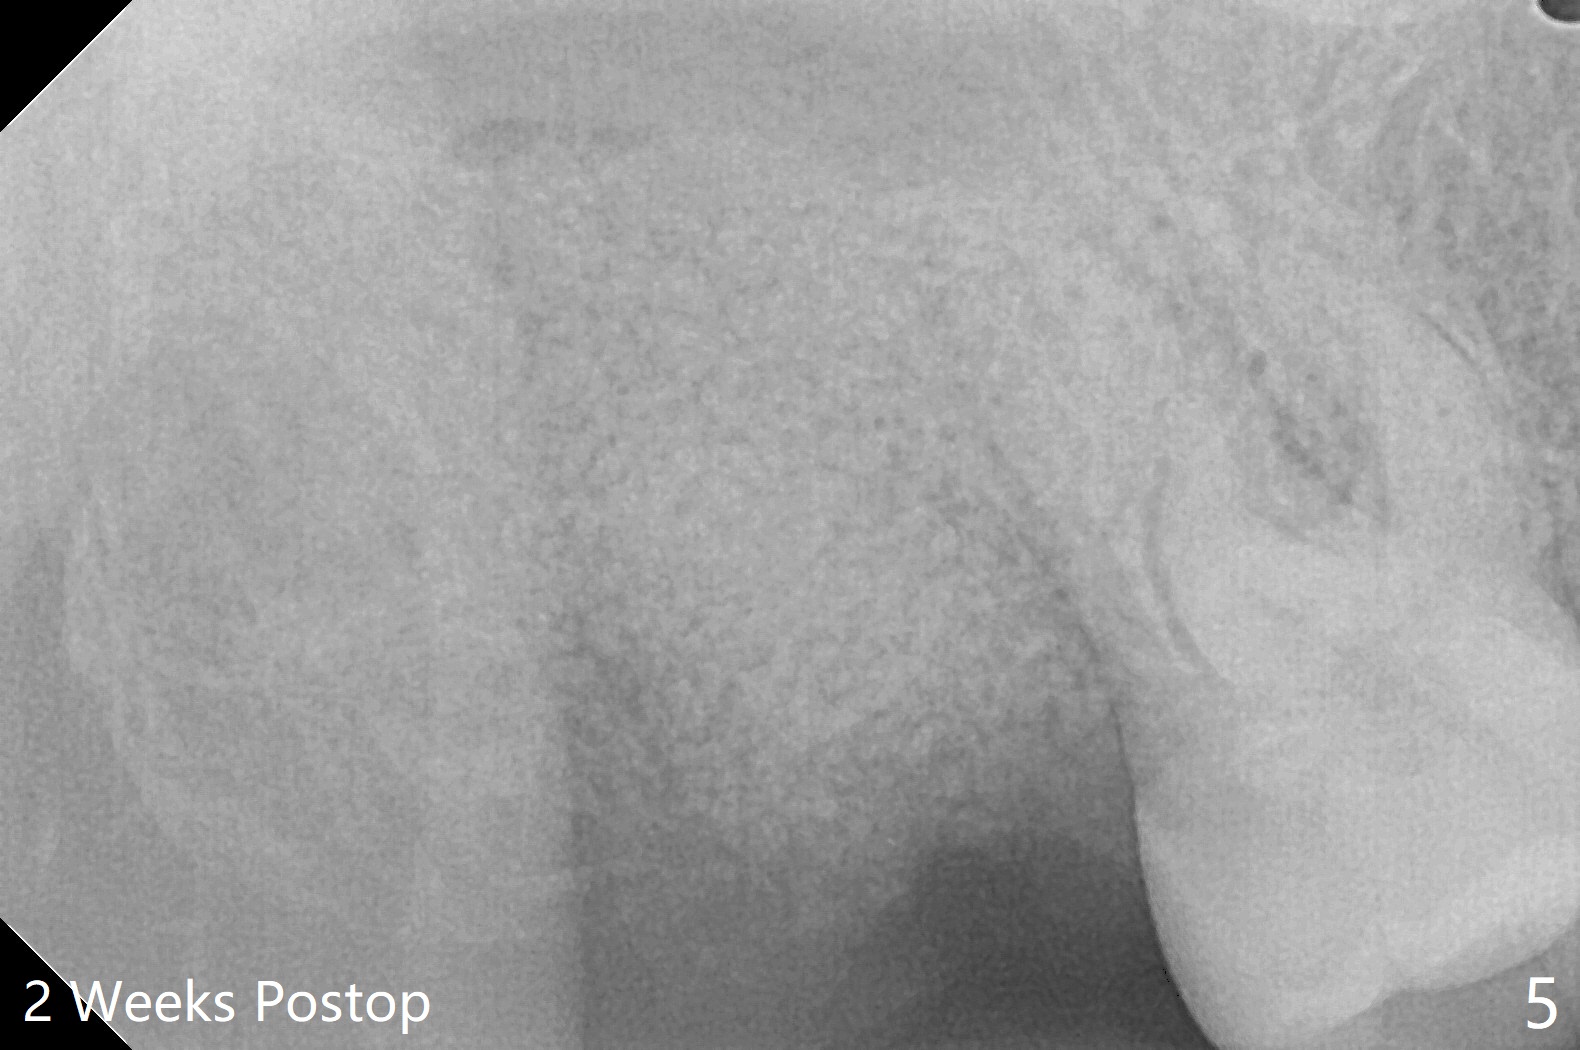

31岁女去年10月份就诊,右上7隐裂(图一),提出根管治疗,牙冠或者拔除,植牙。她犹豫不决,因为今年6月份回国。昨天因腭侧脓肿深度牙周袋复诊,最后同意拔除,植骨。使用GEM21S(血小板因子,没有时间抽血)与皮质骨粉(加一些人工骨)调袢(图二:*),覆盖不可吸收膜(Cytoplast,一张~$50,剪半可用于两个磨牙牙槽窝,买一盒十张,赠送两个PTFE缝线(最近促销);图三)。PTFE,Cytoplast以及Plumber tape据说来自同一个材料,至少前两者最好同时用。但是这个病例,助手打开PGA缝线后,我们才知道Cytoplast刚刚到,它的好处在于暴露于口腔,下面骨粉几乎不会感染。五周后撤除 ,下面骨粉一般愈合正常,接近百发百中。想不到垂直距离特别短,没有空间放置空间保持器,后者有利于牙周敷料固定,下颌第二磨牙牙尖咬到保持器攀(loop),尽管保持器已经放置第一磨牙颈部。无可奈何,在缝线周围涂牙周胶水(图三:蓝紫色)。术后两周膜已经脱落(图四),但是下面骨粉好像没有丢失太多(图五)。两周后伤口愈合(图六)。骨粉失去不多(图七)。